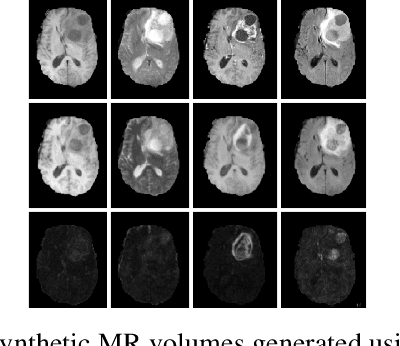

Accurate synthesis of a full 3D MR image containing tumours from available MRI (e.g. to replace an image that is currently unavailable or corrupted) would provide a clinician as well as downstream inference methods with important complementary information for disease analysis. In this paper, we present an end-to-end 3D convolution neural network that takes a set of acquired MR image sequences (e.g. T1, T2, T1ce) as input and concurrently performs (1) regression of the missing full resolution 3D MRI (e.g. FLAIR) and (2) segmentation of the tumour into subtypes (e.g. enhancement, core). The hypothesis is that this would focus the network to perform accurate synthesis in the area of the tumour. Experiments on the BraTS 2015 and 2017 datasets [1] show that: (1) the proposed method gives better performance than state-of-the-art methods in terms of established global evaluation metrics (e.g. PSNR), (2) replacing real MR volumes with the synthesized MRI does not lead to significant degradation in tumour and sub-structure segmentation accuracy. The system further provides uncertainty estimates based on Monte Carlo (MC) dropout [11] for the synthesized volume at each voxel, permitting quantification of the system's confidence in the output at each location.